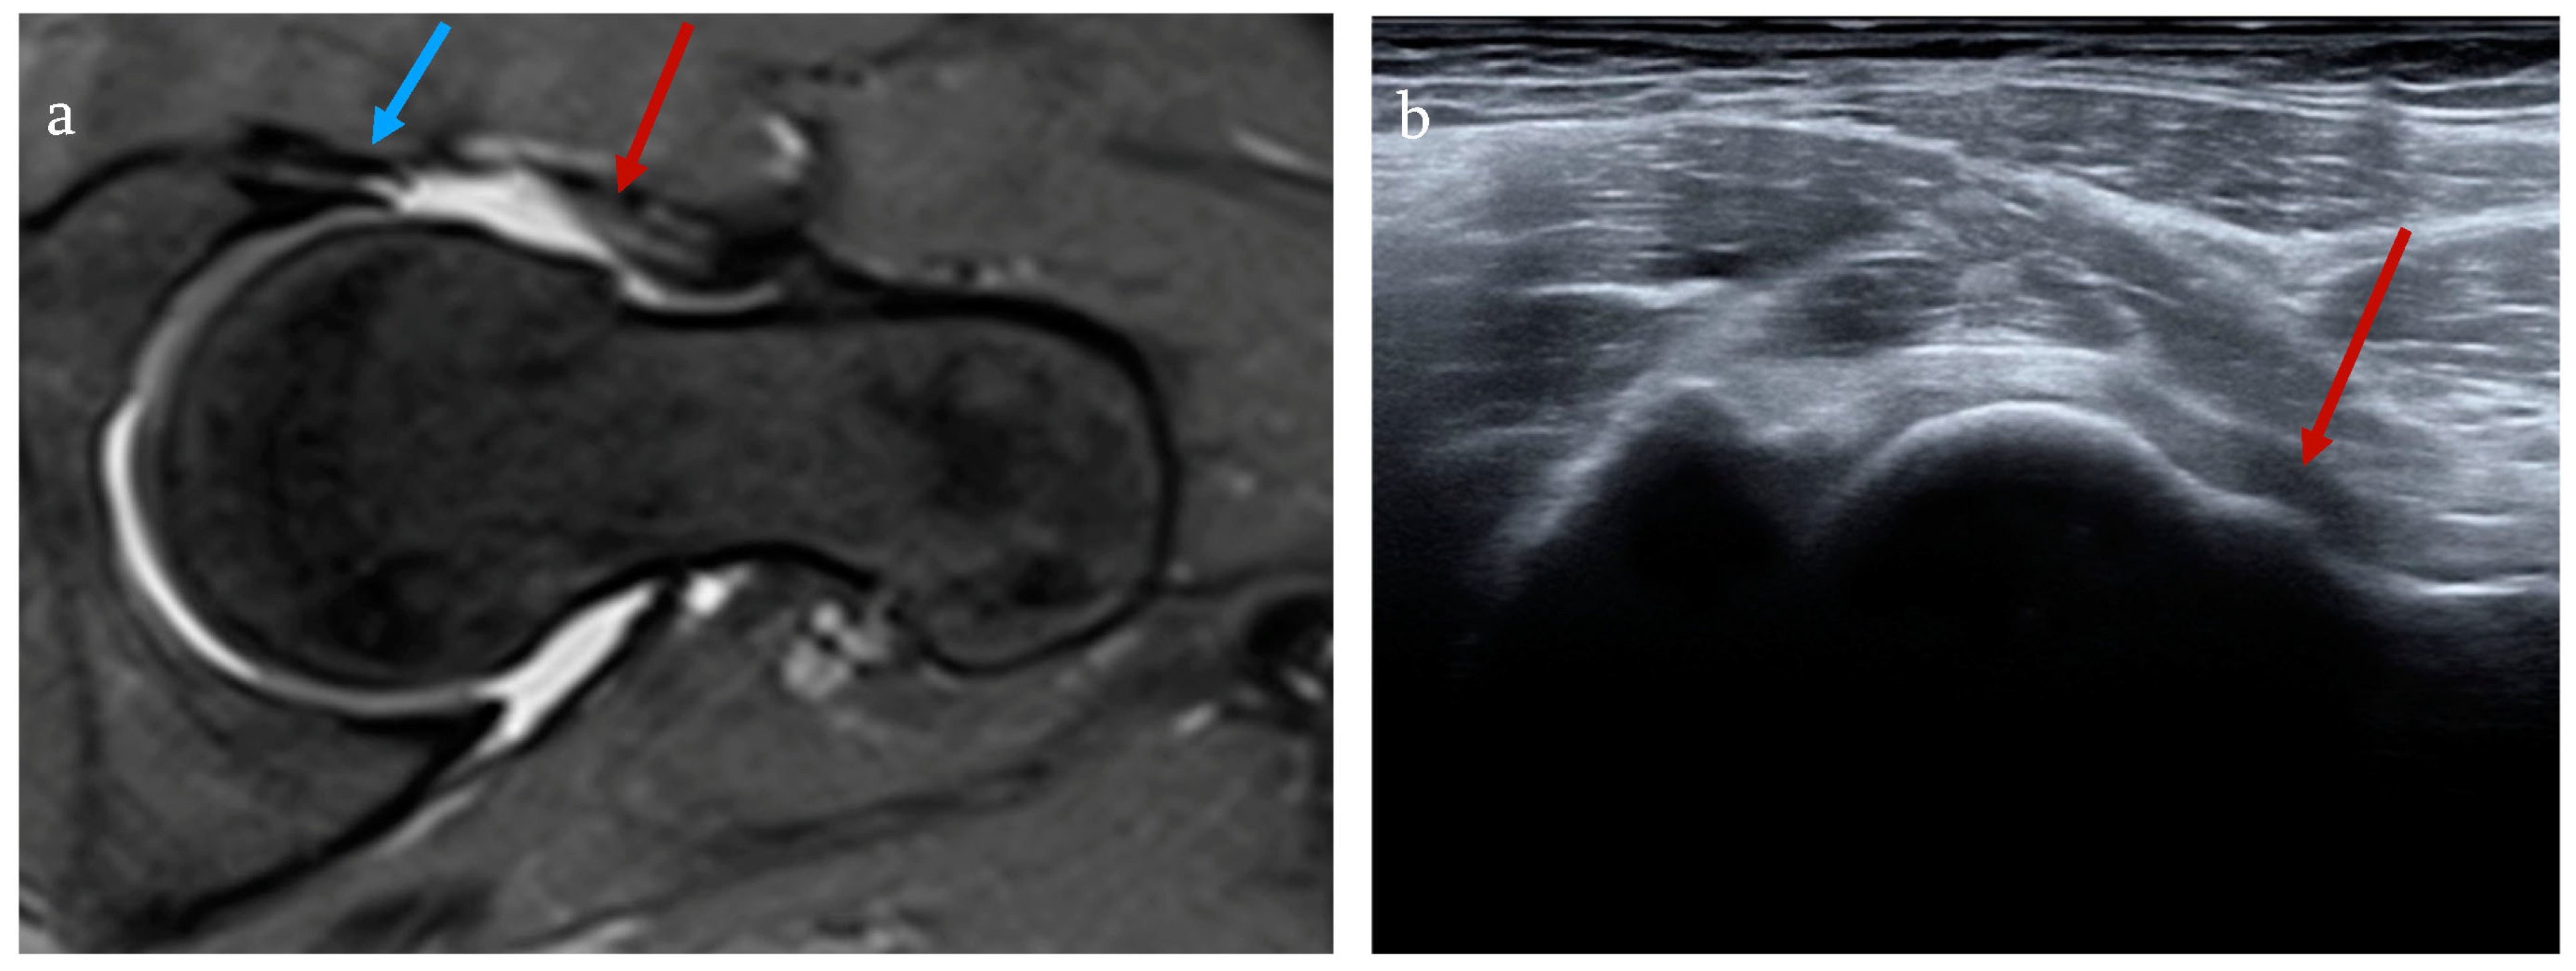

After finishing the ultrasound examination, a contrast-enhanced artho-MRI of the pathological hip joint was performed to detect lesions of the labrum and secure a diagnosis of femoroacetabular impingement. In all patients who were included in this study, an artho-MRI was completed using the parameters of 15 mL of intraarticular 2 mM gadolinium solution in the following sequences: axial FSE T1 Fat-Sat, coronary SE T1, coronary T2 Fat-Sat, sagittal FSE DP, axial three-dimensional (3D) DESS with radial reconstruction along the longitudinal axis of the femoral neck, or radial FSE DP image (2D) orientation being based upon the longitudinal femoral neck axis. Lesions of the labrum were diagnosed by both an orthopedic surgeon as well as a radiologist. Clinical examination and further diagnostics excluded other underlying pathologies explaining the presented symptoms (Figure 2).

Figure 2.

FAI with cam deformity (red arrow) and labral tear (blue arrow). Contrast-enhanced arthro-MRI (a) and ultrasound in anterior longitudinal section (b).